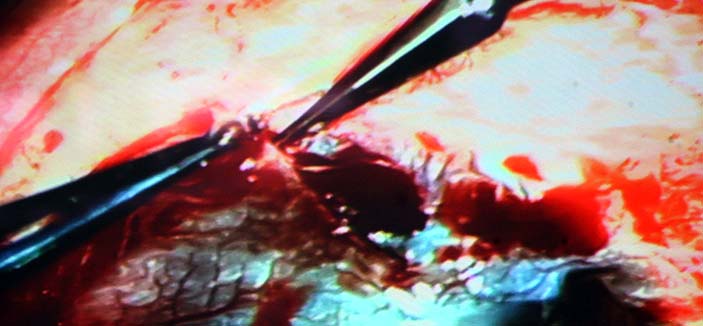

ترشيح المملكة لتكون بداية انطلاق جمعية الشرق الأوسط للقرنية برئاسة د. الطويرقي

«الجزيرة» تقف على إجراء أول عمليات زراعة الخلايا الجذعية بتخصصي الملك خالد للعيون        1 / 6 Showing image 1 of 6   الجزيرة - علياء الناجي: الجزيرة - علياء الناجي: في سابقة هي الأولى من نوعها، تقف وسائل الإعلام على أُولى عمليات زراعة الخلايا الجذعية في المملكة. وقد وقفت «الجزيرة» على إجراء العملية وزراعة الخلايا الجذعية لمريض يعاني من اعتلال بقرنيته. ووفقاً للدكتور آشلي بيرنز المدير الطبي التنفيذي بمستشفى الملك خالد التخصصي للعيون خلال تصريحه إلى «الجزيرة»، توجد دراسات مستقبلية لعلاج «الشبكية» بالخلايا الجذعية؛ إذ إنها حالياً تعالج القرنية فحسب. وأكد الدكتور بيرنز أنه يتوقع مستقبلاً أن تكون الخلايا الجذعية لعلاج أمراض عدة، مشيراً إلى وجود 100 حالة حالياً على قائمة الانتظار بالمستشفى، والمختبر الذي افتتح مؤخراً سيسهم بدوره في نقلة نوعية لعلاج القرنية بالخلايا الجذعية. وفي ظل الإنجازات المتوالية التي يحققها مستشفى الملك خالد التخصصي للعيون في زراعة القرنيات وزراعة الخلايا الجذعية، فقد تم إعلان إنشاء جمعية الشرق الأوسط للقرنية، وتم اختيار الدكتور عبدالإله بن عباد الطويرقي المدير العام التنفيذي لمستشفى الملك خالد التخصصي للعيون رئيساً لها نظراً لمكانة المستشفى العالمية، والتطور الموجود فيه، وكذلك مواكبة كل جديد في طب العيون وعدد وكفاءة عمليات القرنية والبدء في عمليات زراعة الخلايا الجذعية للقرنية وما يحظي به المستشفى من كوادر طبية وبحثية. والجمعية مفتوحة لانضمام الأطباء لها، إضافة لمجموعة الأساتذة الذين أعلنوا تأسيس هذه الجمعية. وتوجد جمعيات مماثلة في أمريكا وآسيا وأمريكا اللاتينية، الهدف منها هو تطور طب وجراحة القرنية، والتواصل مع الجمعيات المماثلة حول العالم، ودمجها تحت جمعية واحدة. وبيَّن «الطويرقي» قبول رئاسة هذه الجمعية لرفع مكانة المملكة عالمياً وإظهار ما لديها من تقدم طبي وتعليمي وبحثي في طب العيون، وذلك تزامناً مع بدء عمل مختبر الخلايا الجذعية. والأطباء الذين أعلنوا ترشيح د. الطويرقي هم الدكتورة جنيفر إيليسيف أستاذة طب العيون ومديرة مركز هندسة الأنسجة بمعهد ويلمر بجامعة جونز هوبكنز الطبية من الولايات المتحدة الأمريكية، ومن البرازيل الدكتور جوس جومنيز مدير قسم الشدفة الأمامية بجامعة ساو باولو، ومن الهند الدكتور فرندر سنجوان مدير مركز إعادة بناء سطح العين بحيدر إباد، ومن الأرجنتين الدكتور دانيل سوكورستي أستاذ ورئيس قسم طب العيون بكلية الطب بجامعة سلفادور ببوينس آيرس. من جهته، أكد الدكتور عبدالإله بن عباد الطويرقي المدير العام التنفيذي لمستشفى الملك خالد التخصصي للعيون أنه تم إجراء أول ثلاث عمليات زراعة الخلايا الجذعية للقرنية، الأولى لرجل يبلغ من العمر 58 عاماً، والثانية لشاب 28 عاماً، والثالثة لطفلة عمرها 10 أعوام، وجميعهم سعوديون، وكانت العمليات منقولة على الهواء مباشرة لقاعة المحاضرات الرئيسية بالمستشفى. وأضاف د. الطويرقي بأنه تم أخذ عينة من خلايا القرنية للمريض قبل أسبوعين، وقمنا بمتابعتها يومياً في المختبر الخاص بالخلايا الجذعية حتى نمت، وتم بعدها إخضاع المريض المستفيد للجراحة، والحمد لله تكللت العملية بالنجاح بفضل الله، وهذا الإنجاز الطبي متميز على مستوى الشرق الأوسط، ونحن سعداء بأن يضاف مثل هذا الإنجاز لاسم مملكتنا الحبيبة. وقال الدكتور الطويرقي إن نتائج العملية ستكون بعد أسبوعين تقريباً من اليوم، وإن شاء الله النتائج مبشرة. وأضاف: المستشفى بحسب مكانته المتميزة بين مستشفيات العيون في العالم لديه بنك العيون الذي يعتبر فريداً من نوعه، ليس في المملكة فحسب بل في الشرق الأوسط كافة. ومختبر الخلايا الجذعية للقرنية الأول من نوعه في الشرق الأوسط، وهو موجود في بعض الدول الأوروبية واليابان وبعض دول أمريكا اللاتينية. |